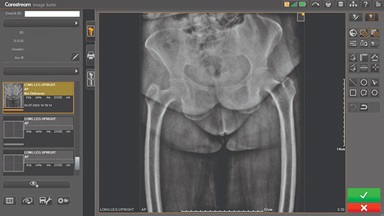

Image Suite V4 MR11 Software

Redefining Workflow Efficiency

By Praveen Rajgopal, Global Product Marketing Manager

CARESTREAM Image Suite V4 MR11 has set a new standard for workflow efficiency, offering a robust set of features and functionalities to enhance clinical confidence in healthcare professionals. Using an auto-generated companion image from a single exposure, leverage a range of image processing options to increase diagnostic accuracy and enhance patient care.